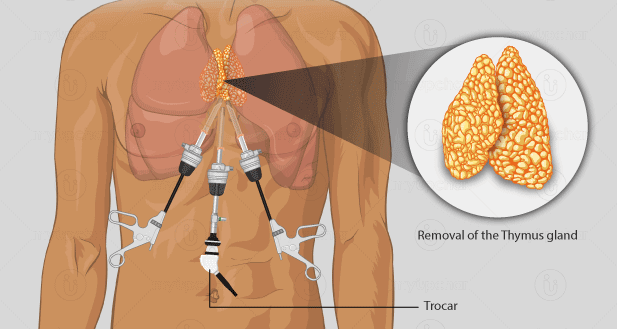

Overview

Package includes:

Days in hospital : 7 to 8 Days (For patient and one attendant)

Days in hotel : 14 Days (For patient and one attendant)

Room type in hospital : Shared

Room type in hotel : Private

Hotel category: Standard

Value added benefits of the Thymectomy:

Ø Doctor consultation charges

Ø Lab tests and diagnostic charges

Ø Room charges inside hospital during the procedure

Ø Surgeon Fee

Ø Nursing charges

Ø Hospital surgery suite charges

Ø Anesthesia charges

Ø Routine medicines and routine consumables (bandages, dressings etc.)

Ø Food and Beverages inside hospital stay for patient and one attendant.

Extra benefits:

ü Interpreter

ü Visa assistance

Ø Site tourism of the city

Ø Follow up with the doctor

Ø Airport pick up and drop

Ø Free online consultation with the doctor

Ø Priority appointments with the doctor

Ø Room upgrade from sharing to private